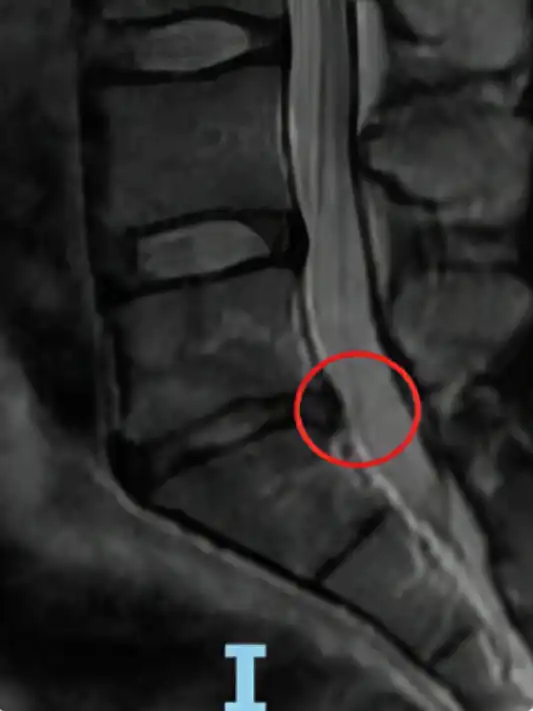

Las resonancias de un paciente antes y después de las sesiones con la bomba diamagnética. El paciente ha realizado 15 sesiones de bomba diamágnetica. Después la hernia discal ha desaparecido.

Otro ejemplo: Antes y después de 15 sesiones con la bomba diamagnética.

La hernia grande (extruida) ha desaparecido del todo (100%)